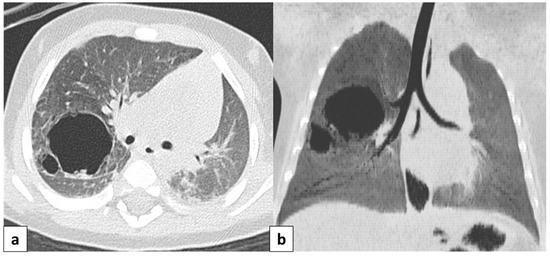

3.4.5. Bronchogenic Cysts

3.5. Vascular Anomalies

Pulmonary Arteriovenous Malformation